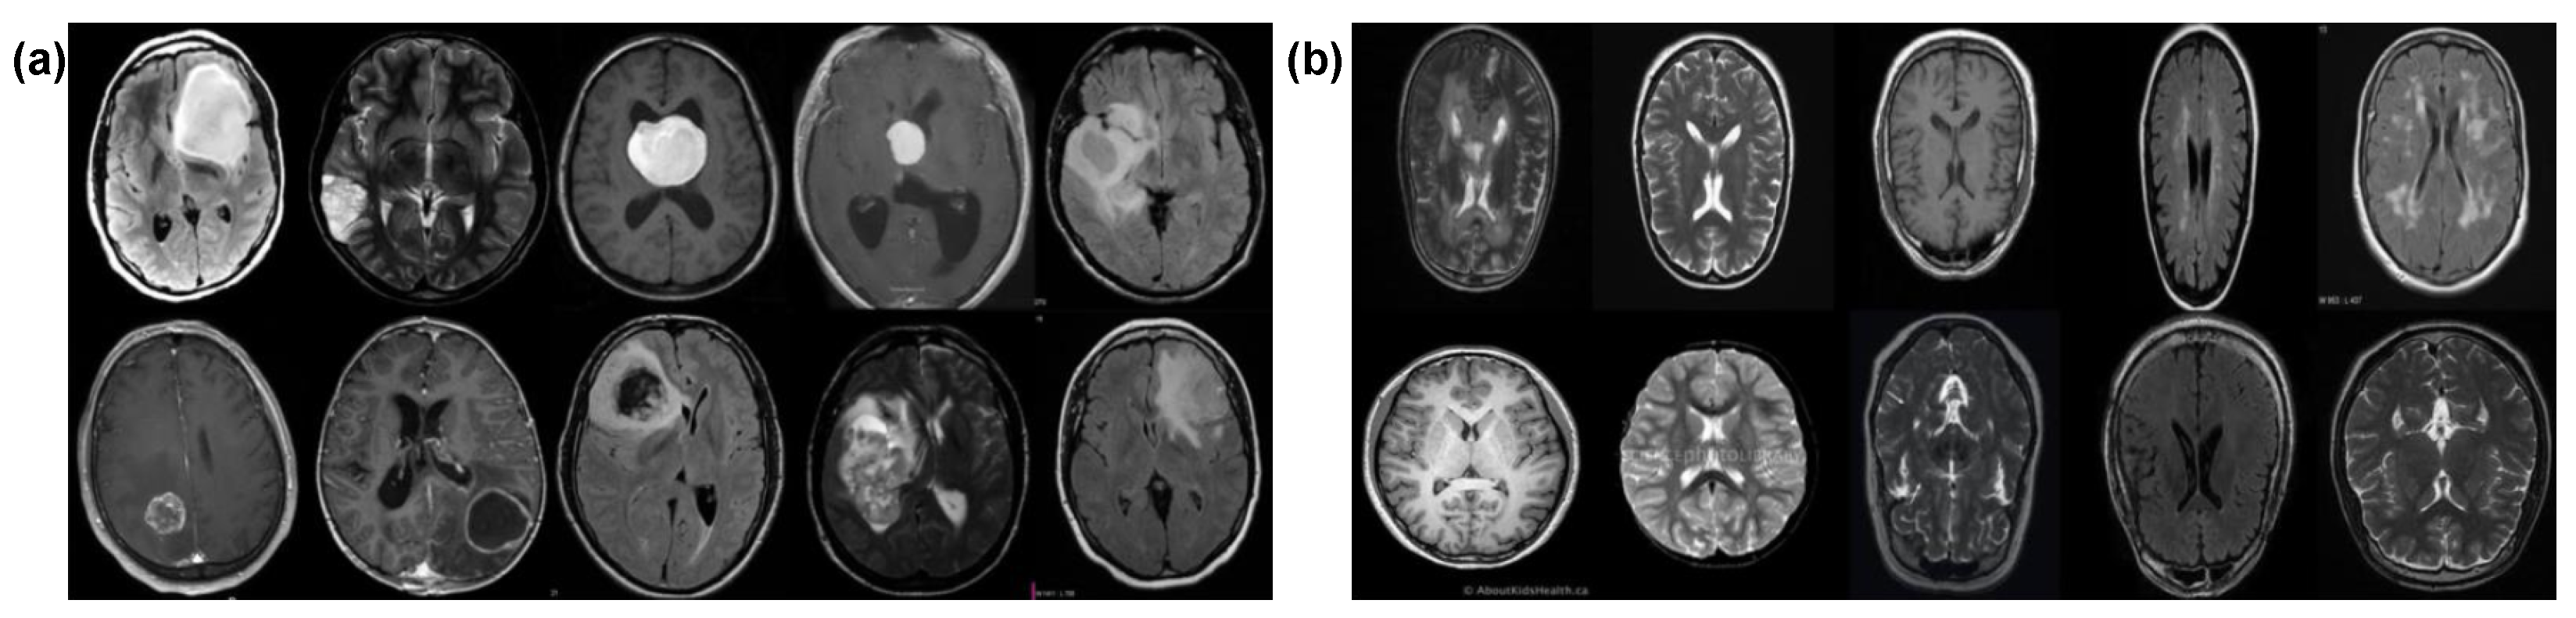

3.1. Dataset Description

| Class | Images | Train | Validation | Label |

| Cancerous | 1500 | 1200 | 300 | 1 “Yes” |

| Non-Cancerous | 1500 | 1200 | 300 | 0 “No” |

| Total | 3000 | 2400 | 600 |